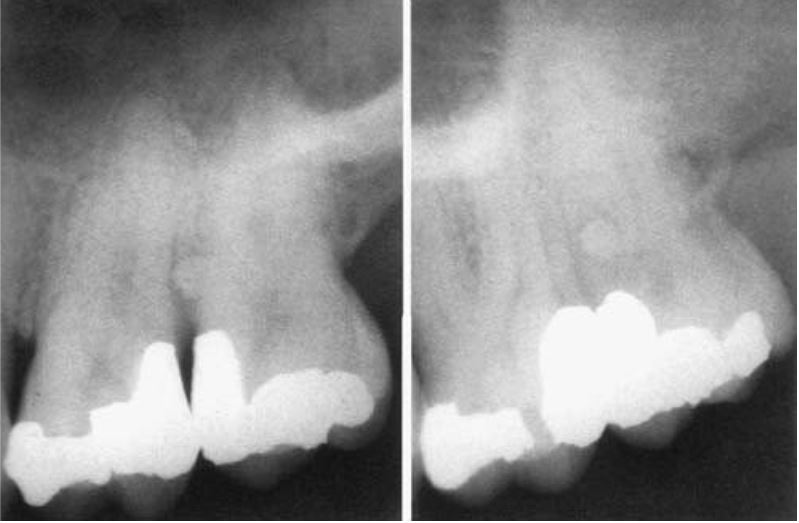

Men răng mở rộng về cổ răng (cervical enamel extension)

Xảy ra ở đường nối men – cement mặt ngoài các răng cối lớn. Phần men mở rộng có dạng hình chữ V, trơn láng hoặc nhám và mở về phía vùng chẽ.

Các răng cối lớn hàm dưới gặp nhiều hơn hàm trên. Khó chẩn đoán dựa trên X quang, mà phát hiện được dựa vào đầu thám trâm hoặc cây thăm dò nha chu. Men răng mở rộng này thường gây túi nha chu và bệnh lí vùng chẽ, khi viêm nhiễm sẽ tạo thành nang, gọi là nang chẽ ngoài (buccal bifurcation cyst).

Nang được đặc trưng bởi khối thấu quang hình bán nguyệt, chồng lên chân răng ngoài, đôi lúc nang mở về phía xa. Trên phim mặt nhai thấy răng bị đẩy về phía trong.